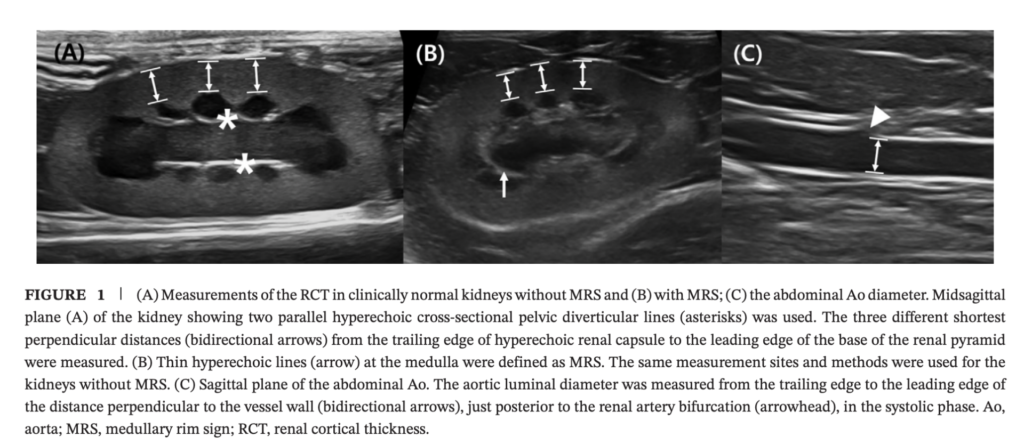

測定方法

ここは実臨床でかなり参考になります。

RCTの測り方

- 腎のmidsagittal plane

- 2本の平行な高エコーのpelvic diverticular line が見える断面を使う

- 腎被膜の trailing edge から、renal pyramid 基部の leading edge までの最短垂直距離

- ventral側で最も見やすい3か所を測って平均

- cranial pole / caudal poleに限定しない

という方法です。

つまり、先生がよく感じるような

極の部分の edge shadowing を避けて、見やすいventral cortexを複数点測る

という設計になっています。ここは実践的です。

大動脈径の測り方

- sagittal plane

- 腎動脈分岐のすぐ後方

- 収縮期最大径

- 内腔径を trailing edge から leading edge で計測

です。

一応、参考までに測定の際の図を論文から引用して載せておきますね。